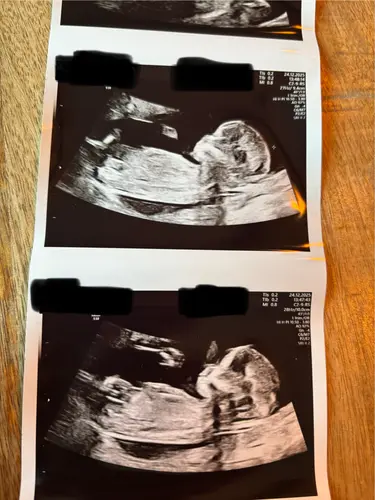

Kan iemand mij helpen bij deze? 14+2 volgende week Officele geslachtsecho maar toch erg nieuwsgierig wat jullie denken hihi:)